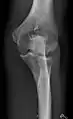

- زانو - AP و جانبی. پروجکشنهای داخلی کندیلار(Condular) در صورت درخواست.

زانوی راست، قدامی خلفی

زانوی راست، جانبی

استخوان کشکک (کمی انحراف) افق مرئی